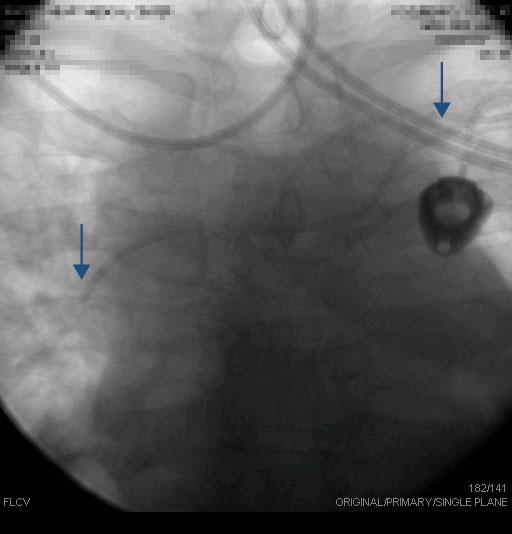

Example of how S.V.C. can be very long in some patients. Right-sided V.A.D. contrast injection. |